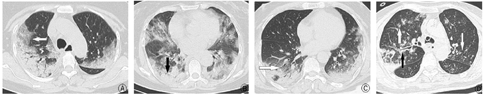

研究组中小叶中心结节或树芽征、支气管管壁增厚、纵隔淋巴结肿大及胸腔积液的构成比低于对照组,差异有统计学意义;研究组中网格影及小叶内间隔增厚的构成比高于对照组,差异有统计学意义(表3)。典型图像见图1。

注:图A、B,重症COVID-19患者,双肺多叶、弥漫分布的磨玻璃密度影,以胸膜下分布为主,小叶内间隔增厚(见白箭头),局部实变(黑箭头);图C,甲型H1N1流感患者,双肺胸膜下分布为主的实变影,局部呈磨玻璃渗出影(见白箭头);图D,重症H1N1流感肺炎患者,双肺上叶见多发小叶中心结节及树芽征(见白箭头),右肺上叶后段支气管管壁增厚(见黑箭头)

A:重症COVID-19患者图像1;B:重症COVID-19患者图像2;C:甲型H1N1流感患者图像;D:重症H1N1流感肺炎患者图像